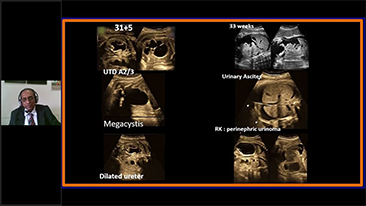

Zoptymalizowane schematy post?powania w badaniach ginekologicno-po?o?niczych s? niezb?dne, aby obs?u?y? du?? liczb? wizyt przesiewowych w poradniach zdrowia dla kobiet. Dla przyk?adu deformacje o?rodkowego uk?adu nerwowego (OUN) to jedne z najcz?stszych wad wrodzonych. Ze wzgl?du na r├│?ne warunki obrazowania, takie jak niewystarczaj?co dobra pozycja p?odu, obrazowanie ?rodkowej p?aszczyzny strza?kowej (MSP, median sagittal plane) jest szczeg├│lnie trudno uzyska? na podstawie klasycznego obrazu USG 2D. Dlatego automatyczne wykrywanie i pomiary mog? znacz?co poprawi? efektywno?? skanowania.